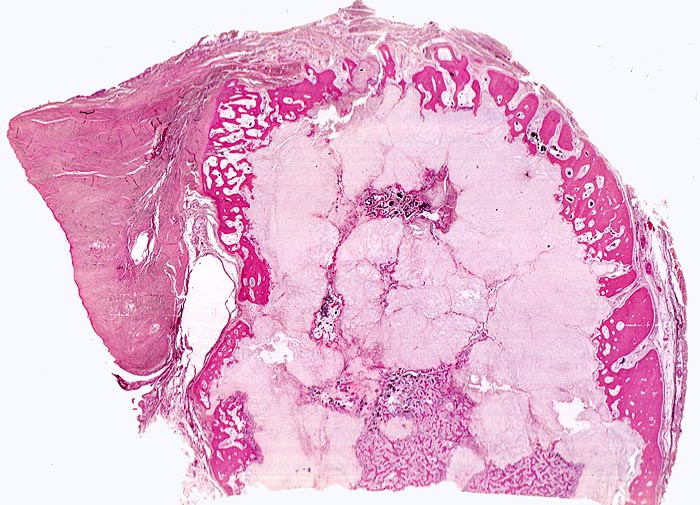

Hochdifferenzierte Chondrosarkome sehen makroskopisch wie reifer hyaliner Knorpel aus. Meist sind die Tumoren lobulär gebaut. Es finden sich gelbe Kalkablagerungen, Pseudozysten und/oder fokale gelatinöse Areale, bei wenig differenzierten Tumoren zusätzlich Nekrosen.

Morphologische Merkmale:

• Von Periost bedeckter kortikaler Knochen.

• Zellarmer lobulierter Knorpeltumor.

• Destruktive Tumorinfiltration des spongiösen und kortikalen Knochens.

• Der maligne Knorpel mit reichlich heller chondroider Matrix gleicht nicht neoplastischem hyalinem Knorpelgewebe.